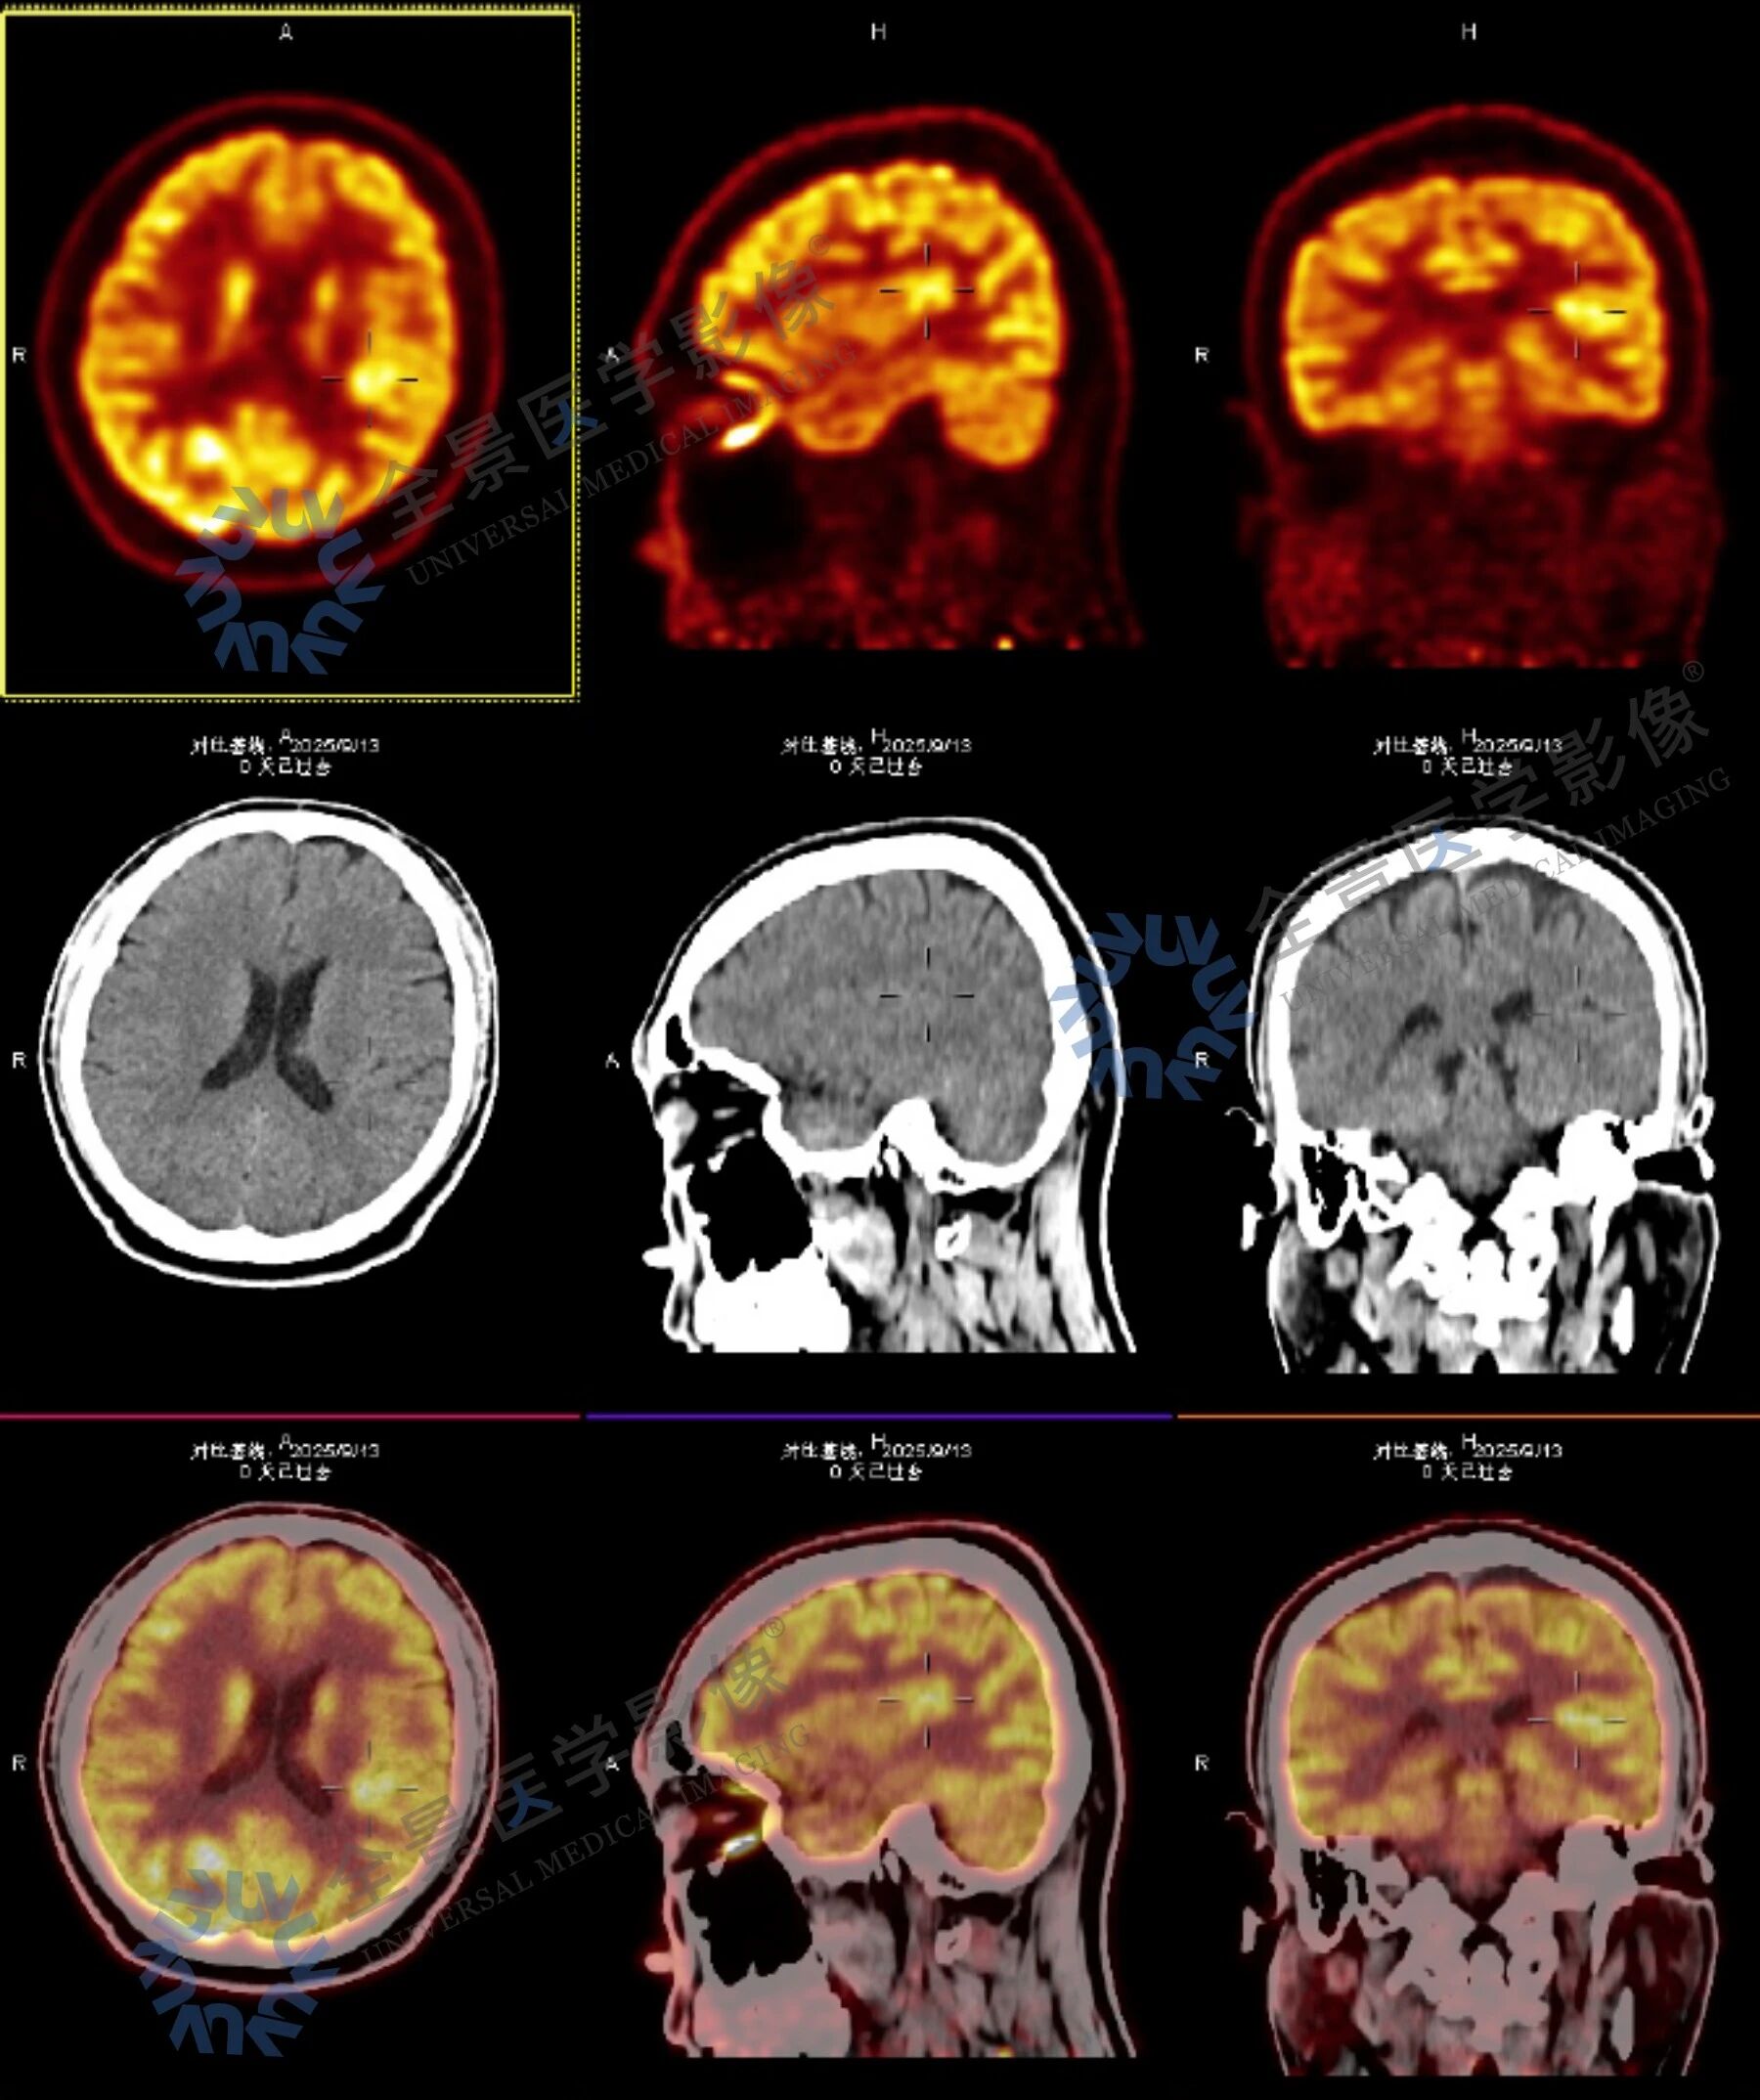

考虑到病症复杂,全景安排门诊部主任与影像主任联合问诊,结合病史和症状,影像主任建议在无创检查前提下,采用结构影像、血流灌注与代谢功能的多模态联合检查,通过脑部 MR 平扫、ASL 脑血流灌注成像与脑部 PET-CT 的融合,实现精准定位与定性诊断。

脑部核磁+ASL 脑血流灌注成像显示:

左侧基底节区异常信号,考虑术后改变,局部脑软化灶周围胶质增生;相应区域 ASL 示灌注稍减低。

脑部 PET-CT 扫描显示:

病灶前缘 MR 异常信号增高,考虑局部神经胶质增生表现;左侧上额叶中部深层较小的类圆形代谢轻中度增高灶及左侧颞叶中部后内侧小片状轻中度代谢增高灶。

结合影像检查结果与临床表现,考虑上述三个部位与头晕发作关系密切,提示存在癫痫可能,以左侧颞叶中部后内侧代谢增高灶为主要病变部位。